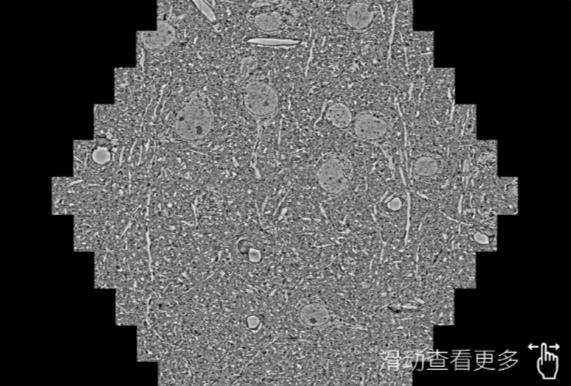

鼠脑切片。左图使用泰安蔡司泰安扫描电镜MultiSEM706对165μmx143pm面积区域成像,耗时仅需1.5秒。右图为鼠脑切片中30μm区域放大效果。样品由芝加哥大学B.Kasthuri提供。

使用蔡司高速泰安扫描电镜MultiSEM对1mm²人脑皮层组织进行高分辨成像,并对其中的各种细胞结构进行三维重构分析。左图展示了2x3mm²组织平面中锥体神经元的三维重构效果。右图显示了局部体积神经元三维重构。图像由哈佛大学chtman实验室提供,渲染图由D. Berger 制作。